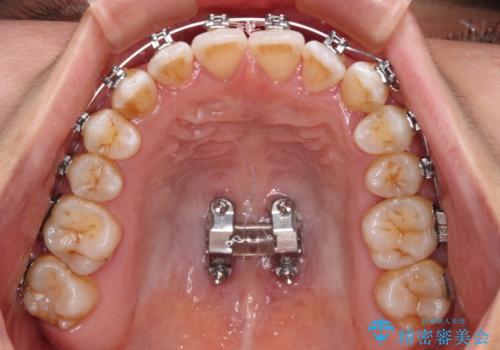

- 矯正装置

- メタルブラケット

上顎歯列および上顎骨が下顎に対して狭小であることが原因であるため、上顎の急速拡大装置を使用して上顎骨を側方に拡大することで反対咬合を改善し、ワイヤー装置で歯列を整えることとしました。

上顎の拡大に伴い反対咬合があっという間に改善されました。